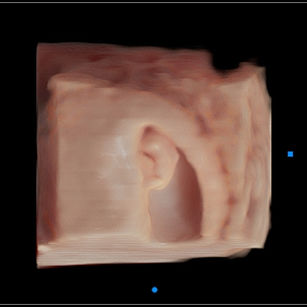

9 Weeks Pregnant

Size: ~0.9 inch (2.3 cm), the size of a Grape!

Development Highlights:

Limbs grow longer; elbows and knees visible.

Tooth buds appear under gums.

Eyes more developed, but eyelids remain fused.

Brain continues rapid development; nervous system forming connections.